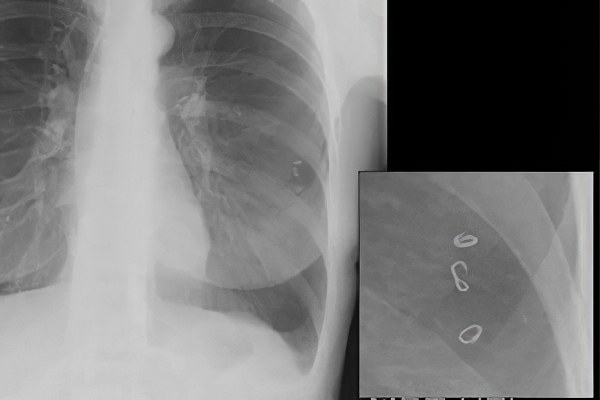

Рентгенография при аскаридозе

Метод используется для выявления изменений в легких и кишечнике. Это доступный и недорогой способ диагностики, который применяется при первых подозрениях на аскаридоз.

Изменения, которые можно увидеть на рентгеновских снимках:

- Рентгенография брюшной полости – позволяет обнаружить скопление кала и газа при кишечной непроходимости. Этот метод помогает отличить аскаридоз от других заболеваний желудочно-кишечного тракта. Однако сами аскариды на рентгеновских снимках не видны.

- Рентгенография грудной клетки – на этом снимке можно заметить изменения в тканях во время легочной стадии аскаридоза (в течение первых 10 дней). Выявляется летучий инфильтрат Леффлера, который меняет свое местоположение через несколько дней. Различия между аскаридозом и пневмонией, а также новообразованиями в легких становятся очевидными при повторной рентгенографии, когда скопления паразитов перемещаются в другую область. Пневмония может развиваться у пациентов с ослабленным иммунитетом как вторичное осложнение основного заболевания.